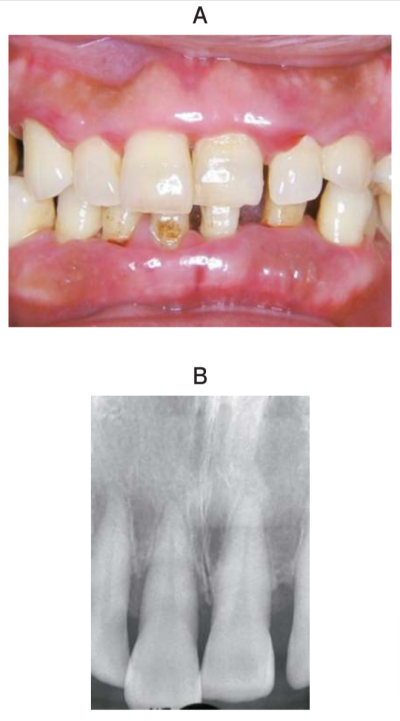

62 歳の女性。上顎前歯部のブラッシング時の出血を主訴として来院した。1年前から自覚していたがそのままにしていたという。1か月前の健康診断で、空腹時血糖は 180 mg/dL、HbA1c は 7.9%であったが、特に治療はしていない。

初診時の口腔内写真とエックス線画像を別に示す。歯周組織検査結果の一部を表に示す。